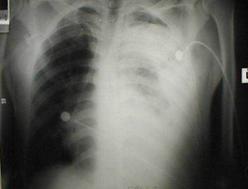

Hemotorace stang masiv Hemotorace stang masiv

Hemotorace

drept masiv Hemotorace stang

Imagine CT Radiografie efectuata in ortostatism